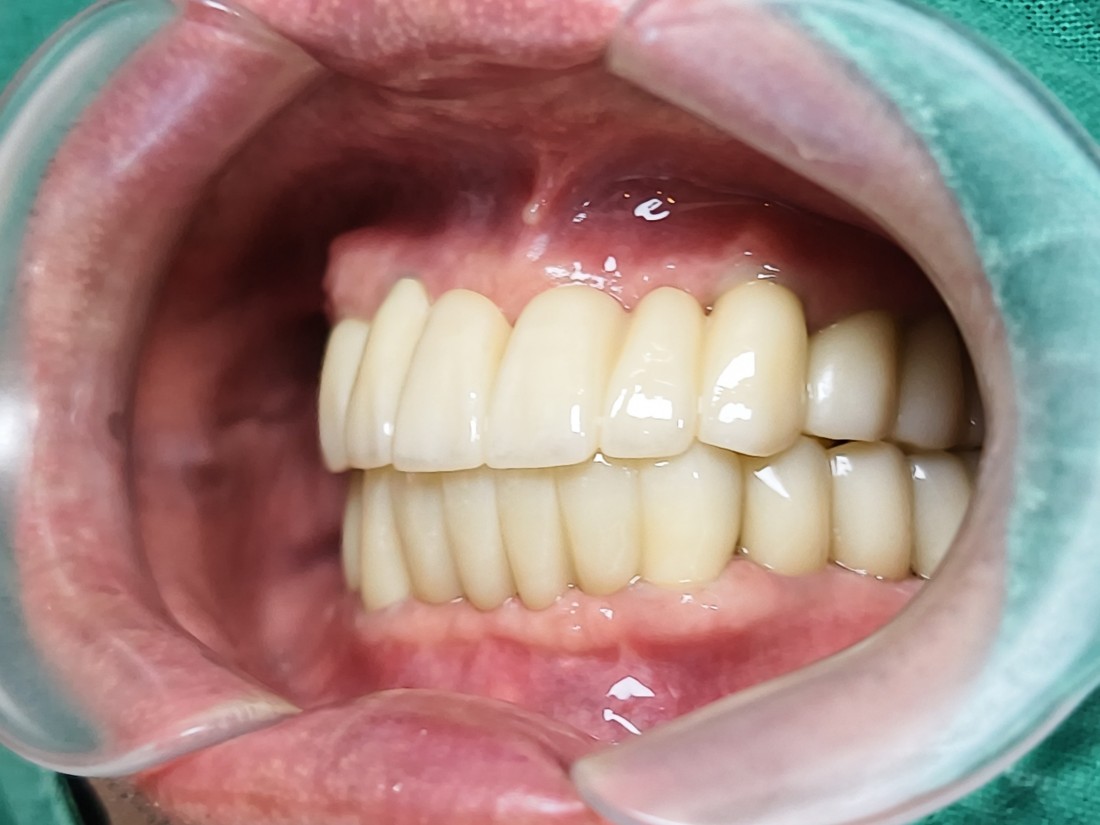

무엇보다도 전체임플란트 중에서

특히 앞니임플란트가

자연스럽고 예쁘게 완성이 되는지

많이 걱정하실텐데요.

광주 전체 임플란트 치과는

4층 자체 치아기공소를 운영하여

보철물 퀄리티를 최상으로 유지합니다.

자연치아보다 더 자연스럽게,

더 잘 씹어질 수 있도록

심미적인 요소와 기능적 요소를

모두 고려하여 제작하고 있으며

불편함이 생기시면 바로 수정이 가능하기 때문에

번거로움 없이 광주 전체임플란트를

완성할 수 있습니다.